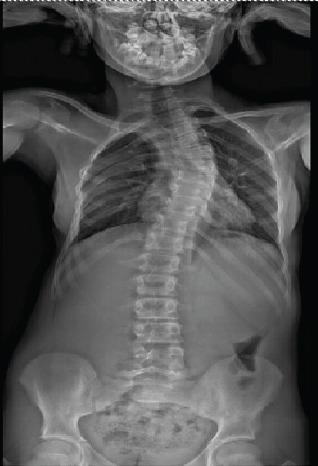

This article illustrates the case of a 13-year-old girl who developed a left thoracic scoliosis caused by ribs fusion, following multiple right thoracotomies during childhood for esophageal atresia with tracheoesophageal fistula. No vertebral abnormalities were reported. Considering the young age of the girl, spinal fusion was not considered. A VEPTR associated with an excision of the fused ribs was used to treat this patient.

The aim of this article was to illustrate the importance of a regular follow-up for the patients who have undergone multiples thoracotomies during their childhood even without vertebral abnormalities and propose an early approach to avoid spinal fusion in early adulthood.